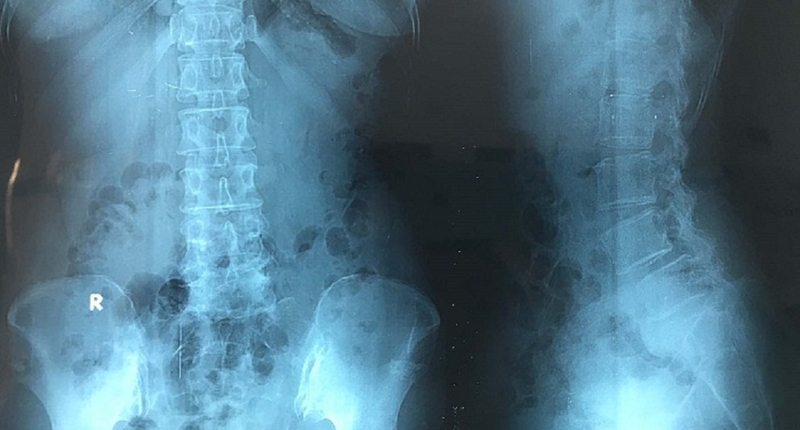

Hình ảnh X quang gai cột sống cho biết điều gì? Cách xác định phương pháp điều trị dựa trên phim chụp X quang

Thông qua hình ảnh X Quang gai cột sống, các bác sĩ có thể xác định được tình trạng hiện tại của cột sống, cũng như biết được chính xác các tổn thương trong cột sống mà người bệnh đang gặp phải.

Dựa vào hình ảnh trên phim chụp X-Quang, chỉ cần thông qua các biểu hiện như đường cong sinh lý tự nhiên của cột sống bị siêu vẹo bất thường, trên thân cột sống xuất hiện các gai xương, tập trung chủ yếu ở phần đầu xương đốt sống, đồng thời đốt sống có dấu hiệu bị xẹp, ngắn hơn so với mức bình thường, phần xương dưới sụn bị đặc lại, lỗ liên hợp có dấu hiệu hẹp đi, đĩa đệm bị xẹp hoặc có dấu hiệu tràn nhân nhầy ra bên ngoài một cách bất thường,… các bác sĩ có thể dễ dàng đưa ra những kết luận cụ thể, rõ ràng về tình trạng bệnh. Chẳng hạn như: Bệnh nhân có bị thoái hóa cột sống hay không, vị trí đốt sống bị thoái hóa, và tình trạng bệnh đang tiến triển ở mức độ nào.

Hình ảnh X quang gai cột sống cho biết điều gì? Cách xác định phương pháp điều trị dựa trên phim chụp X quang 1Thông qua hình ảnh X Quang gai cột sống, các bác sĩ có thể xác định được tình trạng hiện tại của cột sống.

Chụp X-Quang gai cột sống là cách tốt nhất để các bác sĩ thấy đươc những tổn thương nhẹ hoặc dấu hiệu bất thường bên trong cột sống của bệnh nhân. Với công nghệ hiện đại và kỹ thuật y học tiên tiến ngày nay, các bác sĩ chỉ cần dựa vào hình ảnh x quang gai cột sống là đã có thể dễ dàng đưa ra kết luận về tình trạng bệnh tình của bệnh nhân ở thời điểm hiện tại. Từ đó, đưa ra những biện pháp điều trị an toàn, nhanh chóng và hiệu quả nhất.